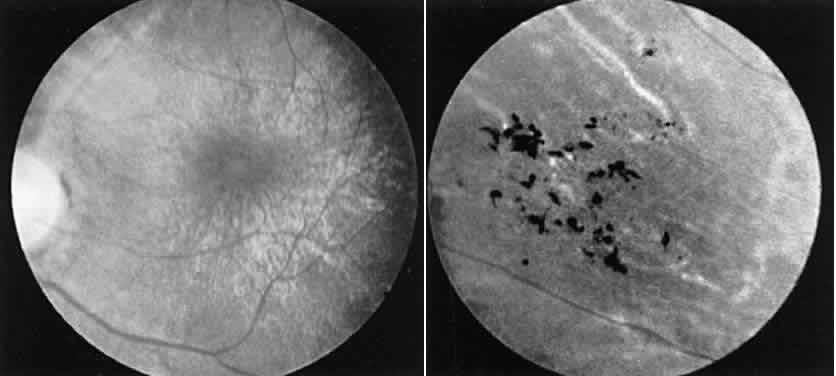

cones will severely affect the ERG. CASE 14 (FIG. 17). A 6-year-old boy was noted at school to have a visual acuity of 20/60 in

each eye. The parents stated that he had no visual complaints. Both

macular areas showed a glistening reflex, which on stereoscopic examination

was found to represent cystic spaces in the foveal-parafoveal area. An

ERG showed a deep negative a-wave but no b-wave (Fig. 18).  Fig. 17. Case 14. See text for details. Left. Macular area. Right. Peripheral retina of another patient with X-linked retinoschisis showing

the diaphanous “veils” or inner layer retinoschisis. Fig. 17. Case 14. See text for details. Left. Macular area. Right. Peripheral retina of another patient with X-linked retinoschisis showing

the diaphanous “veils” or inner layer retinoschisis.

|

These findings are typical of X-linked juvenile retinoschisis. The abnormality

of the ERG probably reflects widespread midretinal changes that

in some cases result in the peripheral inner layer retinoschisis seen

in 50% of such cases.23 In cases without the peripheral schisis vision usually remains in the 20/60 to 20/80 range. As

the patient gets older the central areas of schisis

may flatten leaving a nondescript central retinal pigment epithelium (RPE) change. In

such cases the typical ERG gives the appropriate

diagnosis. |